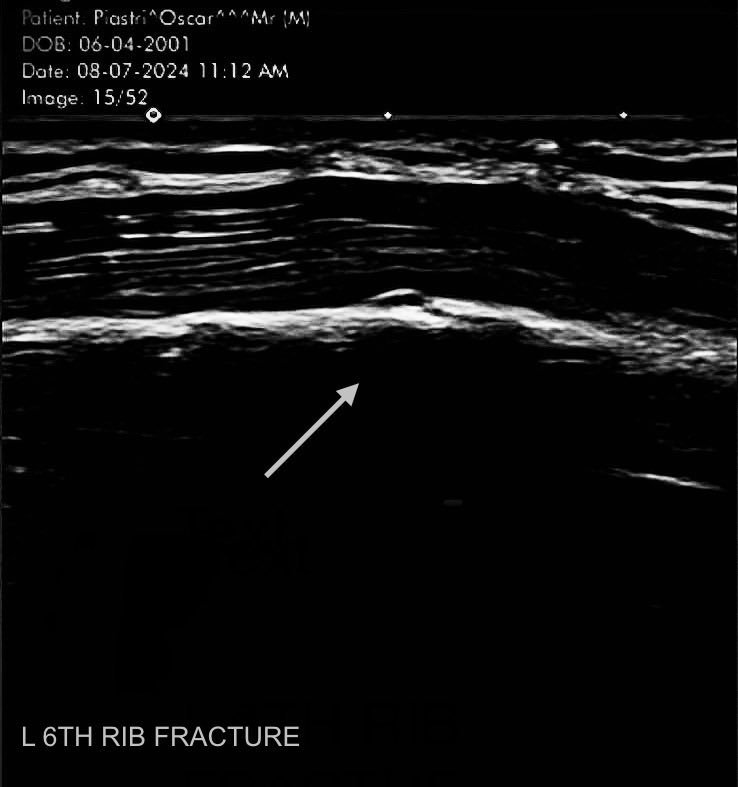

Ganar un Gran Premio en la Formula 1 en un logro único para los conductores jóvenes. Esta temporada, Oscar Piastri se convirtió en el primer piloto nacido en este milenio en subirse a lo más alto del podio. Fue en el Gran Premio de Hungría, donde el australiano le dio a McLaren la segunda victoria del año. Pero la victoria pasa a proeza luego que el “81” anunciara que ese día condujo con una costilla rota.

Piastri le compartió a sus fans que en el circuito de Hungaroring, fue el piloto más rápido de todos pese a tener una costilla rota. Así lo hizo saber una publicación a través de sus redes sociales. «Primera parte de la temporada completada. Primera victoria en un GP. Primer hueso roto. Costillas disfrutando del parón», publicó.

La fecha de esta radiografía data del 8 de julio de este año. Lo que significa que se la hizo el lunes después del Gran Premio de Gran Bretaña. En aquella carrera, Piastri acabó cuarto y parece que salió de Silverstone con una lesión. Dos semanas después, llegó el GP de Hungría, donde se pudo ver al de McLaren sin ningún problema aparente. Logró su primera victoria en el Gran Circo con una costilla rota.